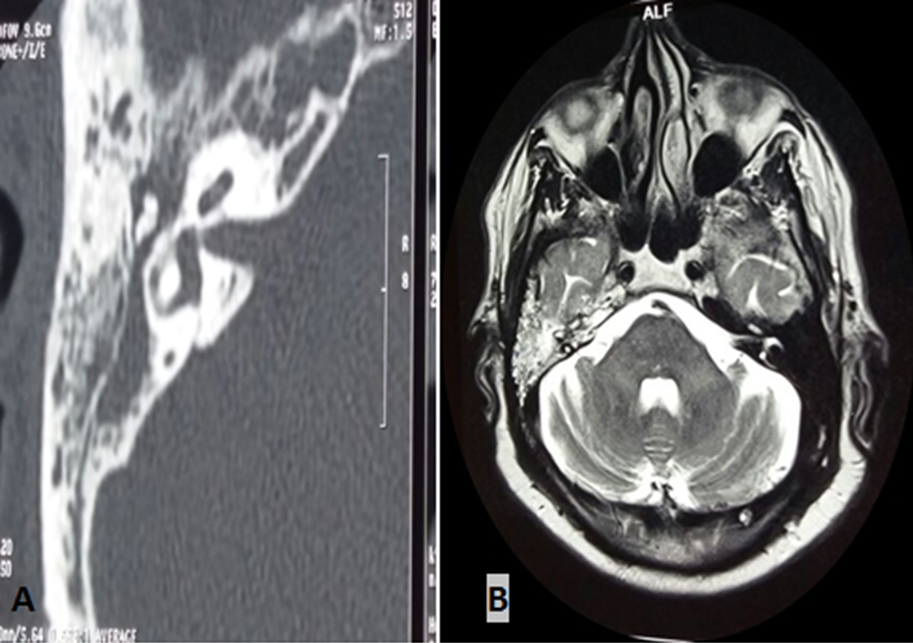

Les paragangliomes tympaniques sont des tumeurs bénignes fréquentes de l’oreille moyenne, faites de cellules neuroendocrines, dispersées le long des axes vasculaires de la tête, du cou et de la colonne vertébrale. Une hypoacousie et un acouphène pulsatile en sont souvent les symptômes révélateurs. L’otoscopie révèle souvent une masse rougeâtre pulsatile rétro-tympanique. L’IRM et la scintigraphie aux analogues de la somatostatine (octréo-scan) sont les examens radiologiques de choix. L’octréo-scan permet de rechercher les autres localisations. Le dosage des dérivés méthoxylés urinaires est nécessaire, complété par le dépistage des autres composantes des néoplasies endocriniennes multiples (NEM). La biopsie est contre-indiquée, vu le risque hémorragique. La chirurgie est le traitement de choix. Nous rapportons le cas du patient FA, 75 ans, admis pour paragangliome tympanique, révélé par une hypoacousie droite installée depuis 4 ans, associée à des acouphènes pulsatiles concomitantes aux battements cardiaques. Otoscopie: masse rétro-tympanique droite rougeâtre battante (A). (B) Comblement totale de l’oreille moyenne et des cellules mastoïdiennes, sans processus tumoral individualisable, avec hypersignal franc en diffusion, qui se rehausse de façon intense après injection de produit de contraste (PDC). Le bilan de NEM s’est révélé sans anomalies, notamment les dérivés méthoxylés de 24h, parathormone et calcitonine. Le diagnostic de paragangliome a été retenu, vu que le rehaussement intense après injection de PDC. Le patient est prévu pour octréo-scan avant la chirurgie.